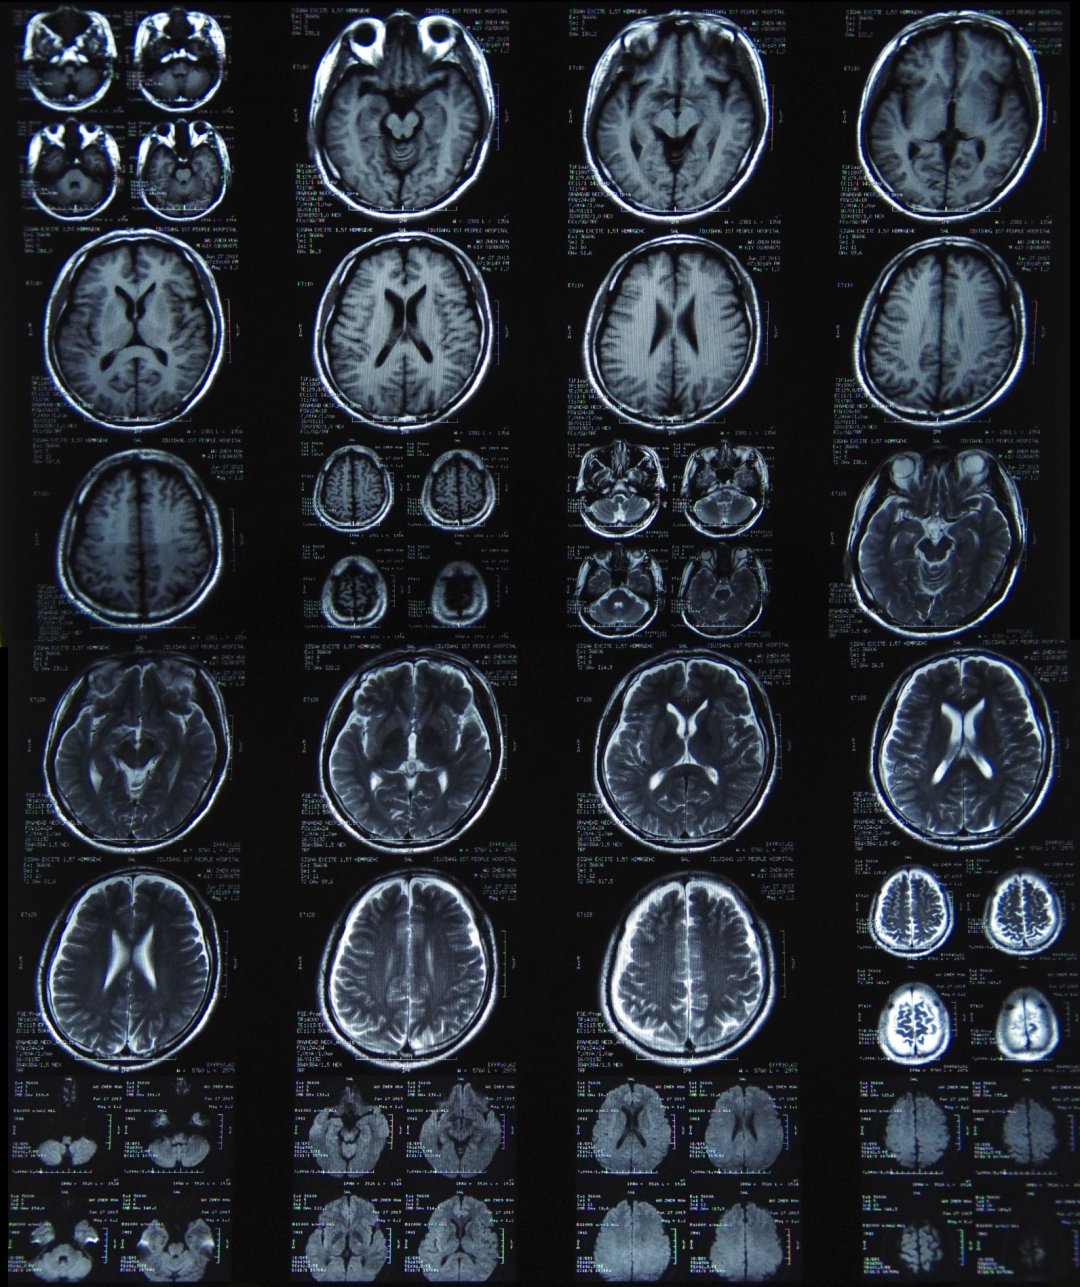

其實包括在內很多做過MRI的朋友都可以看到,早年間國內醫院的核磁共振儀器,尤其是高端核磁共振儀器主要來自進口,西門子、GE等公司的標誌可以説是隨處可見。

核磁共振掃描儀是大醫院裏不可或缺的醫療設備,在心腦血管、神經和腫瘤等多種重大疾病影像診斷方面起着重要作用。

而國內醫院高額採購國外的MRI設備,其實也是一種“被教育”的過程。因為不可否認的一點是,以往(甚至當前)國外MRI設備的性能就是好,成像就是快、就是清晰。

中華放射學分會傳染病學組組長、北京佑安醫院影像中心兼放射科主任李宏軍教授在接受《人民日報》採訪時候表示之前的國產核磁共振儀器:**在線圈的信號採集技術不過關,**只能依賴進口。這導致整個MRI系統不僅全週期壽命“價格昂貴”,而且“預定設備週期時間也長”。

同時國產MRI對於高場強磁共振系統對磁體、屏蔽系統和冷卻系統等方面的技術要求更高,技術還不夠完善。這次的重心主要是基於射頻線圈製作、磁體國產化和新序列技術等磁共振關鍵技術國產化後量產的有AI進行數據分析和處理的高端MRI。

此外據央視新聞報道,這台我國自主研發的核磁共振儀器已經應用於北京大學深圳醫院,它還可以將儀器工作的情況實時傳輸到 15 公里外的中國科學院深圳先進技術研究院進行分析。也就是説,這一次我們不光突破了硬件的高端化,還實現了軟件的智能化和醫療聯網治療。

早在央視報道出來的前幾個月,這款高端國產的MRI設備就已經入駐了協和醫院。使用的反饋當然也滿是好評。

隨着我們國家這款自主研發的,擁有124項先進專利的核磁共振儀量產,高端MRI設備的價格門檻也將從3000萬元下探至260萬元。直接實現了價格的白菜化,使相關檢查費用逐漸降低,廣大人民羣眾看病的花費也會隨之減少。